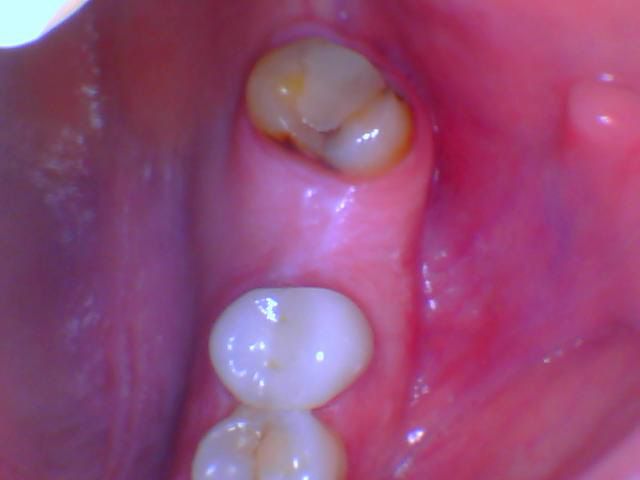

To secure an ill-fitting denture

Dental implants serve as a foundation to secure unstable dentures which results in better stability and functional performance. The innovative method stops the denture from shifting while eliminating discomfort so patients can experience better confidence and simple eating and speaking abilities.